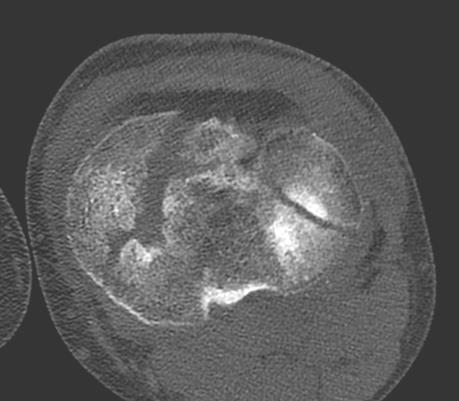

Złamanie okolicy stawu kolanowego o morfologii przedstawionej poniżej, u 52-letniego mężczyzny, bez obecności masywnych uszkodzeń okołostawowych tkanek miękkich, najkorzystniej leczyć jest:

Pytanie 52